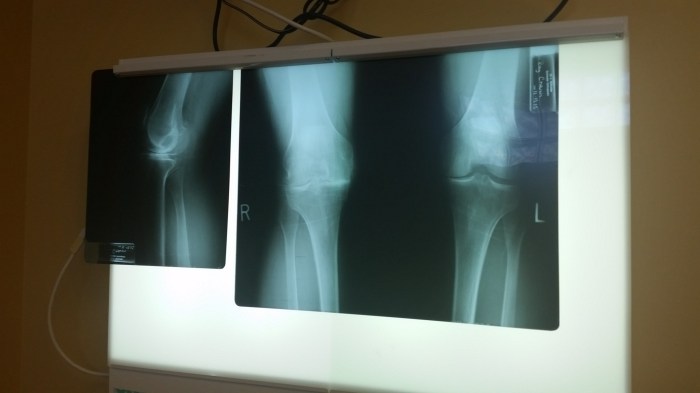

We traveled to Tennessee last week to meet with Dr. Lawrence Schrader, an orthopedic surgeon who will be doing a full knee replacement on Roy in the near future. His very advanced surgical technique makes him the perfect doctor for Roy. Roy saw our primary care doctor in Hammond this week for pre op things and surgery clearance and so far all is well. When the surgery is scheduled we’ll stay in Bartlett, Tennessee (outside of Memphis) for a couple of weeks while he recovers enough to drive Dora, our RV home. You can see from the X Ray that his left knee still has a cushion between the bones but his right has none. We hoped for a partial knee replacement but it is obvious he really needs a full knee replacement.